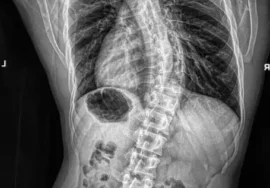

يتساءل كثير من الأهالي عن العلاقة بين اعوجاج العمود الفقري (الجنف) وصحة العظام لدى الفتيات المراهقات، وهل يمكن أن يزداد الانحناء سوءًا مع الوقت نتيجة ضعف العظام. دراسة علمية شاملة أجريت على 919 فتاة تتراوح أعمارهن بين 11 و16 عامًا كشفت عن وجود ارتباط واضح بين شدة الانحناء ونقص كثافة العظام، مما يجعل متابعة الحالة والتدخل المبكر أمرًا بالغ الأهمية.

سعى الباحثون لمعرفة ما إذا كانت الفتيات المصابات بانحناء العمود الفقري يعانين أيضًا من نقص كثافة العظام (Osteopenia)، الذي قد يزيد من خطر تفاقم الانحناء مع الوقت. لتقييم ذلك، تم تقسيم الفتيات إلى ثلاث مجموعات:

مجموعة انحناء متوسط: زاوية كوب (Cobb angle) بين 10 و39 درجة.

مجموعة انحناء شديد: زاوية كوب 40 درجة أو أكثر.

شدة الاعوجاج ترتبط بنقص كثافة العظام

كلما زادت زاوية الانحناء، انخفضت كثافة العظام بشكل ملحوظ في العمود الفقري والساقين، مما يزيد من مخاطر هشاشة العظام مستقبليًا.نمو غير متوازن في الأطراف

بدءًا من عمر 13 عامًا، كانت أذرع وساق الفتيات المصابات بالجنف أطول من الفتيات السليمات، مما قد يسبب خللاً في التوازن الجسدي ويؤثر على الحركة اليومية.ارتفاع معدل الإصابة بهشاشة العظام

الفتيات المصابات بانحناء شديد لديهن نسبة أعلى من نقص كثافة العظام مقارنة بالمجموعة ذات الانحناء المتوسط، ما يعني أن مراقبة كثافة العظام ضرورية لدى الحالات الشديدة.ارتباط مباشر ومستقل

حتى بعد تعديل النتائج بحسب العمر والطول، استمرت العلاقة بين شدة الانحناء وضعف العظام، مما يؤكد أن الانحناء نفسه يؤثر على صحة العظام وليس فقط نتيجة عوامل أخرى.

الفحص بالأشعة: لتحديد زاوية الانحناء (Cobb angle) وكثافة العظام، ما يساعد على التخطيط للعلاج المناسب.